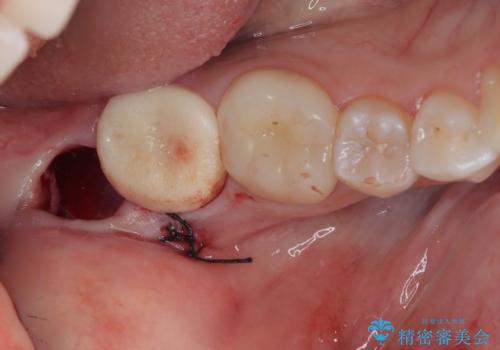

CTで神経の走行位置を確認し、抜歯術を行いました。

1週間後に抜糸を行っています。

局所麻酔をしっかり効かせて抜歯を行うため、治療中の痛みはありません。術後の痛みに対してはお薬を処方します。

- 外科手術のため、術後に出血、痛みや腫れ、違和感を伴います